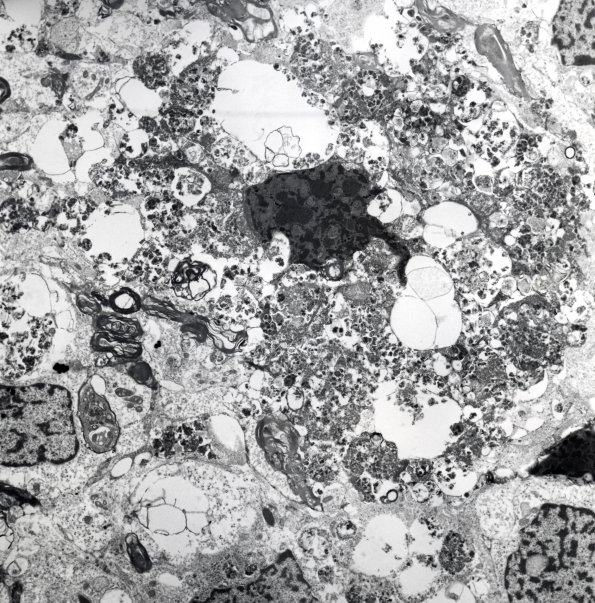

Ultrastructural examination demonstrates the granularity of tumor cells results from the accumulation of autophagosomes (Electron micrograph)